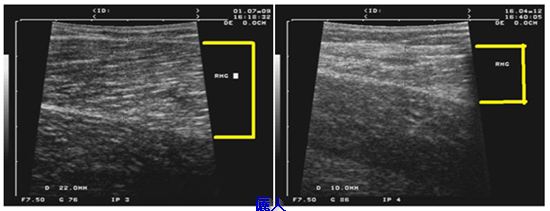

其他蘿蔔腿的報導追踨時間常常是幾個月而已,我們會長期追踨我們的案例,以下是做完肌肉雕塑手術術前(左)與術後二年九個月(右)的內腓超音波圖。術前是2.2cm,術後是1cm,即使是男性病人,肌肉並沒有長回來或手術造成小腿功能影響。